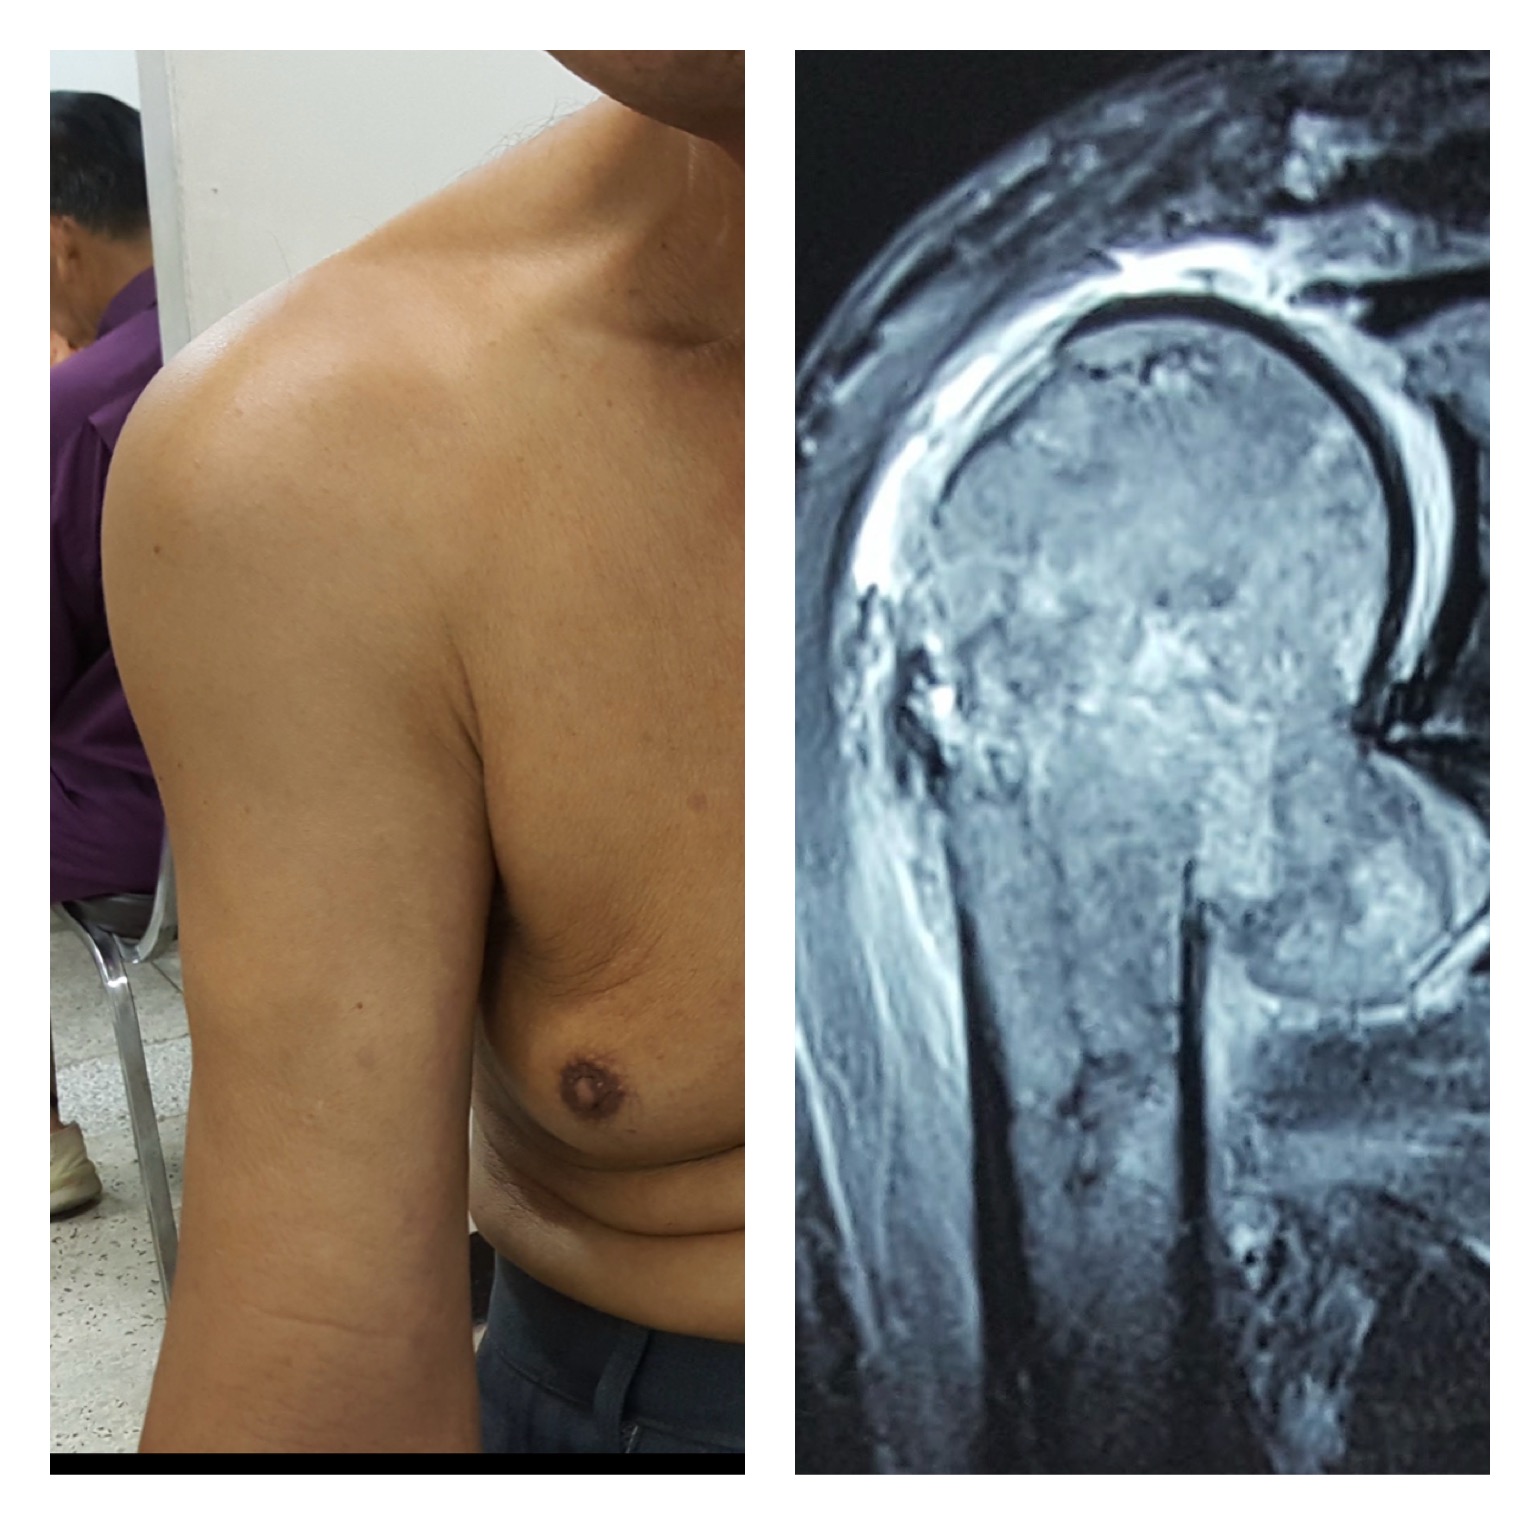

🔹 2) MRI ไหล่

บอกขอบเขตของเนื้องอก การลุกลามสู่กล้ามเนื้อ เอ็น และเส้นประสาทได้ละเอียดมาก

- เนื้องอกร้ายบริเวณหัวกระดูกต้นแขนเป็นโรคที่ต้องวินิจฉัยด้วย MRI และตัดชิ้นเนื้อ